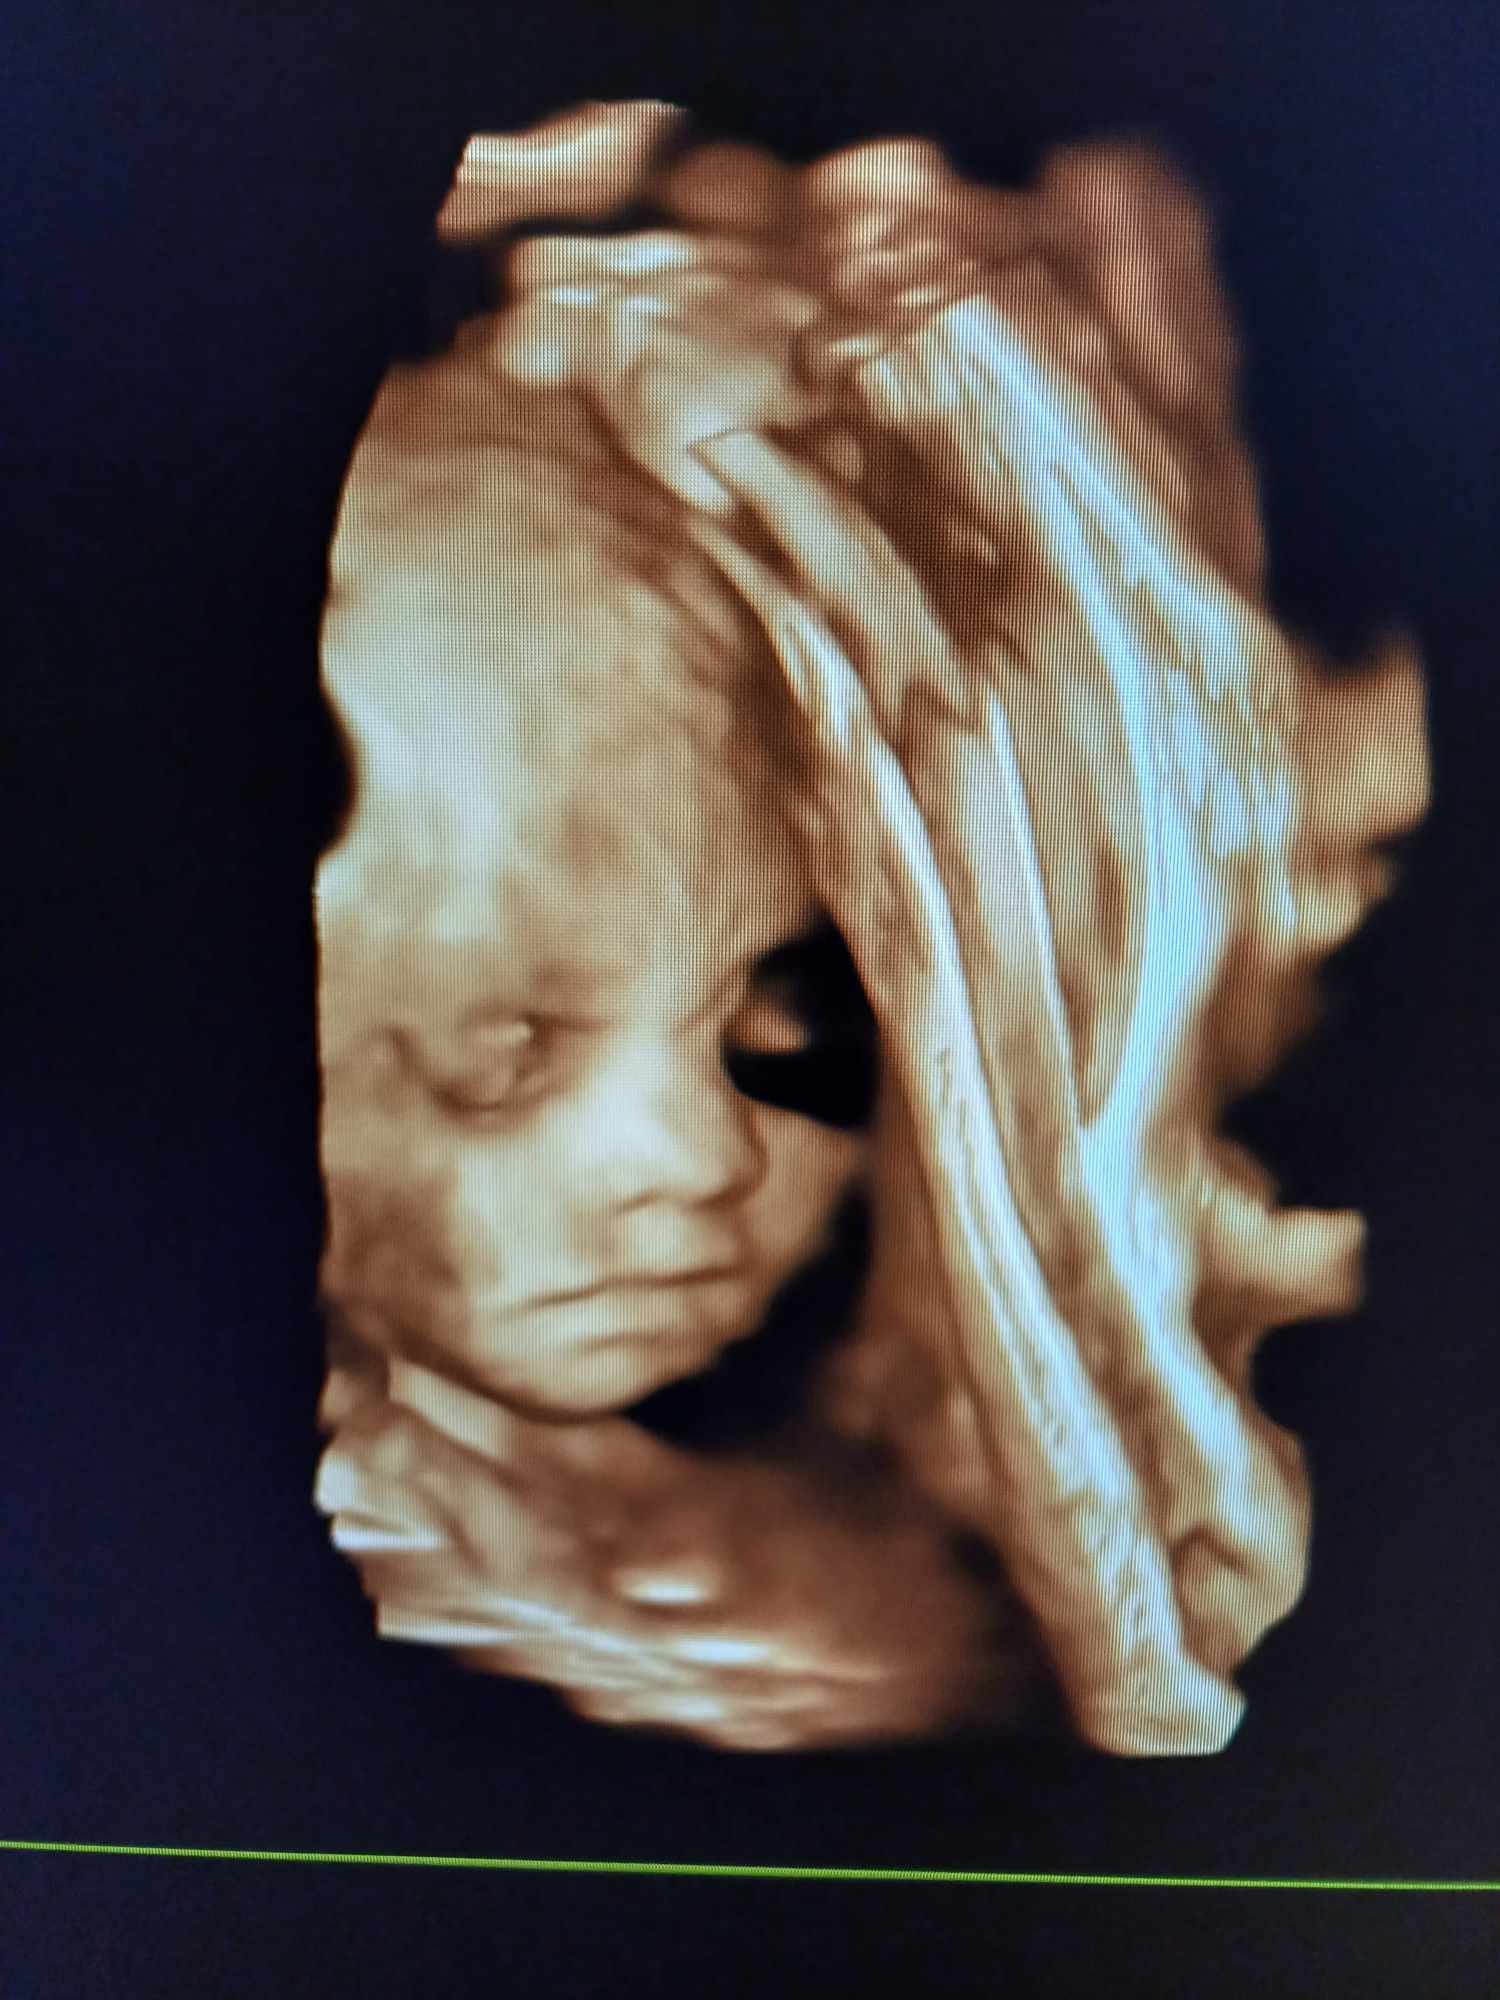

Pozrite si fotky z nášho moderného pracovného prostredia

Naša gynekologická ambulancia je vybavená modernou technikou a poskytuje pacientkom príjemné a komfortné prostredie pre všetky druhy vyšetrení a konzultácií.